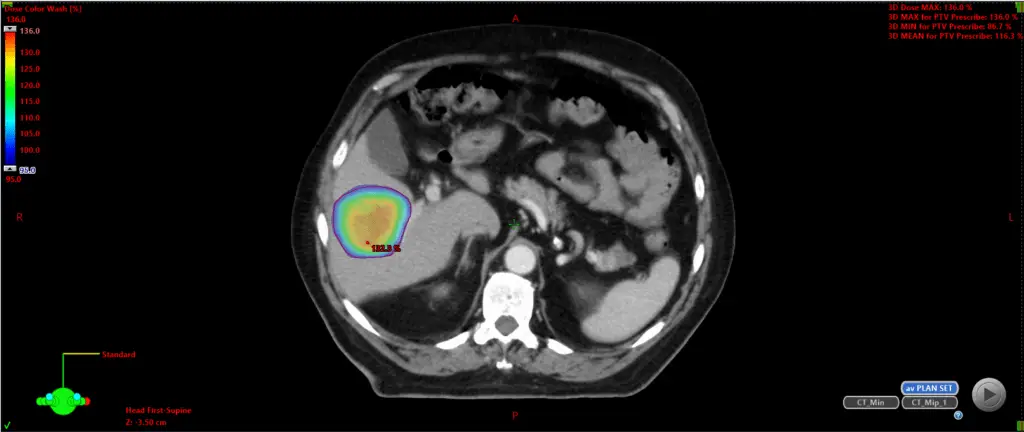

Stereotactic radiotherapy is a highly accurate form of high-dose radiotherapy, typically delivered in a limited number of sessions – usually between one and five. This treatment has a high chance of reducing or completely removing the cancerous area being targeted. The precision of the radiation dosing means that the side effects associated with SABR are generally negligible.

It is essential to acknowledge that while side effects can arise with SABR, they are generally mild and transient, causing minimal disruption to most patients’ daily routines. The frequency and severity of side effects can fluctuate based on factors such as the size and location of the tumour, the dose of radiation administered, and your individual health concerns. Common mild to moderate side effects, such as fatigue, are typically well-tolerated and manageable with supportive care measures. Before commencing treatment, I will provide you with a contact number that offers access to support and care around the clock, should you have any concerns about your symptoms.